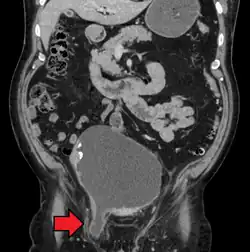

Medical imaging

A physician may diagnose an inguinal hernia, as well as the type, from medical history and physical examination.[20] For confirmation or in uncertain cases, medical ultrasonography is the first choice of imaging, because it can both detect the hernia and evaluate its changes with for example pressure, standing and Valsalva maneuver.[21]

When assessed by ultrasound or cross sectional imaging with CT or MRI, the major differential in diagnosing indirect inguinal hernias is differentiation from spermatic cord lipomas, as both can contain only fat and extend along the inguinal canal into the scrotum.[22]

On axial CT, lipomas originate inferior or lateral to the cord, and are located inside the cremaster muscle, while inguinal hernias lie anteromedial to the cord and are not intramuscular. Large lipomas may appear nearly indistinguishable as the fat engulfs anatomic boundaries, but they do not change position with coughing or straining.[22]